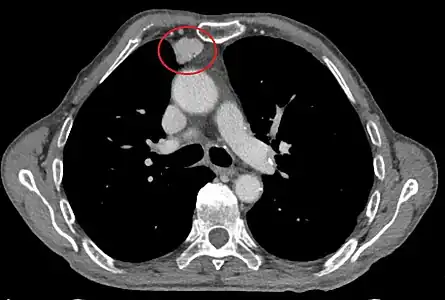

Scanner injecté, en fenêtre médiastinale, montrant un carcinome thymique envahissant les structures médiastinales :

1 : tumeur hétérogène, aux contours irréguliers, présentant des plages hémorragiques ;

2 : veine cave supérieure ;

3 : tronc artériel brachiocéphalique ;

4 : artères sous-clavière gauche et carotide commune gauche ;

5 : crosse de l'aorte ;

6 : sternum.